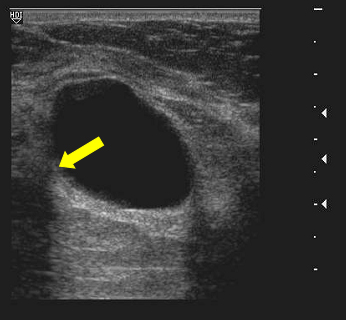

Echogenicity- Anechoic

echo free, its all black

air in lungs or fluid in bladder